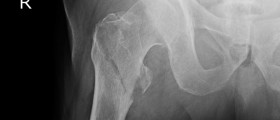

After knee replacements pain, swelling, and bruising are a part of recovering process.A complete knee replacement surgery takes a large toll on the body and so you can't perform your daily activities in a norman manner.